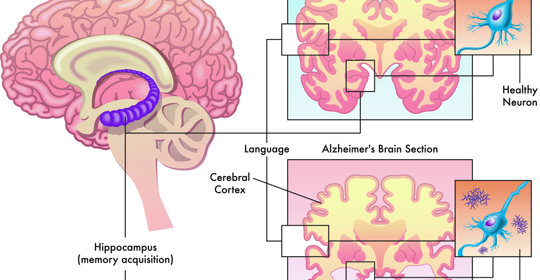

家族性澱粉樣多發性神經病變變、症狀與治療